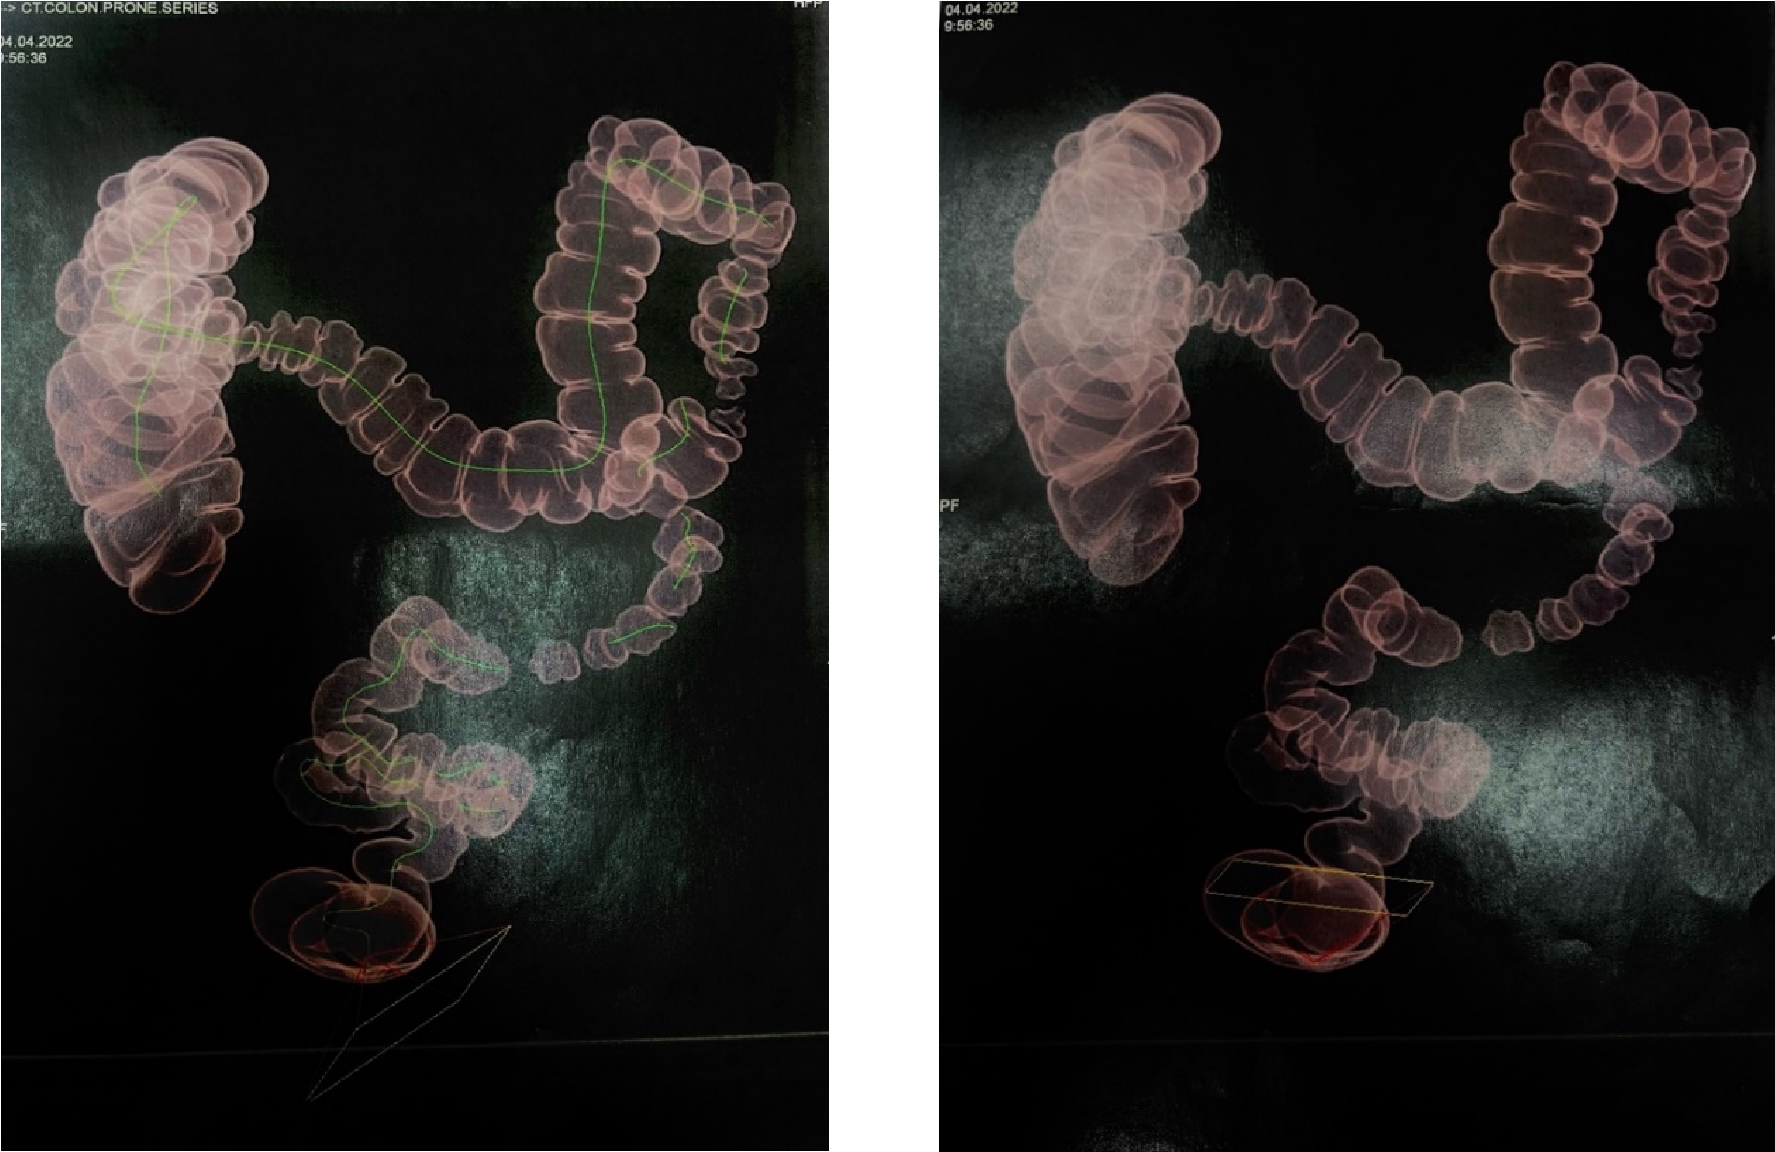

Рис. 1. Диффузные изменения паренхимы почек. Двухсторонний нефроптоз

Рис. 2. Трансверзоптоз, конгломерат из спаянных между собой отделов ободочной кишки в области печеночного угла.

МСКТ виртуальная колоноскопия от 04.04.2022

КТ-признаки дивертикулов толстой кишки с проявлениями дивертикулита. КТ-признаки хронического колита. КТ-признаки умеренной долихосигмы, трансверзоптоза